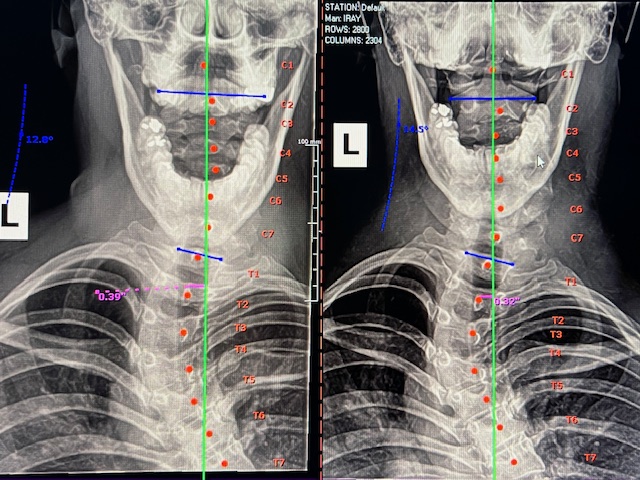

• X-rays

This allows chiropractors to get a clear view of the curvature of the spine and identify any abnormalities.